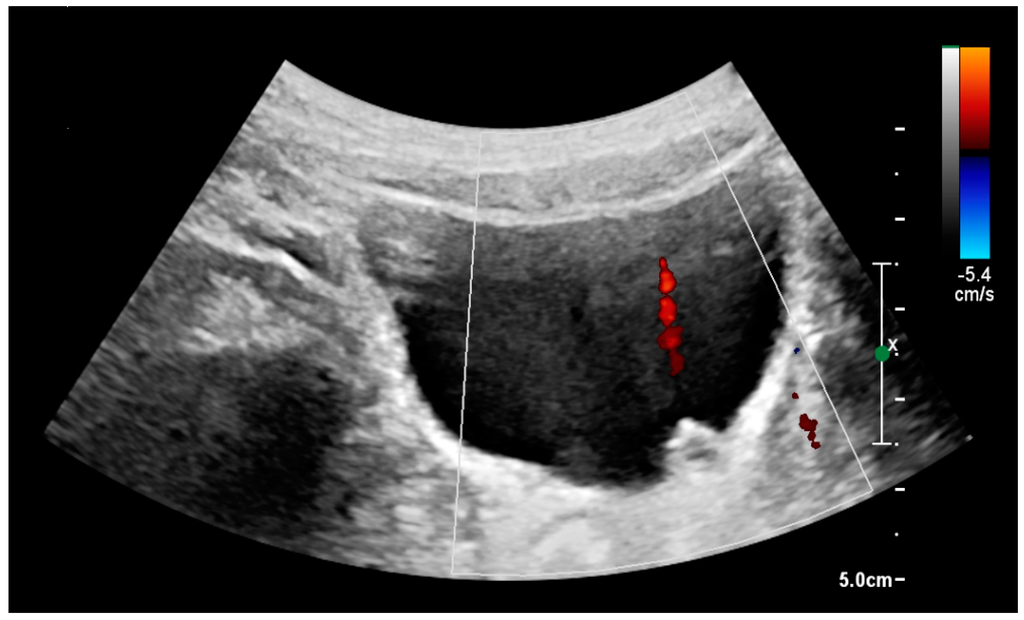

Figure 21. Left hydroureter with ureteric jet. No stone is visible. The red color in the color box represents motion towards the transducer as defined by the color bar.